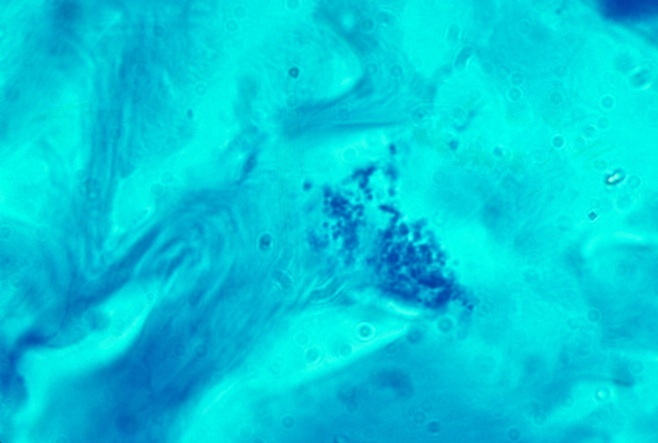

These bacterial clusters can infect a cell in small numbers, or they can be so tightly-packed into a cell that they obscure the nucleus. In addition, the coccoid forms may appear as scattered extracellular forms, far removed from any cell. I observed star cells in breast cancer (Fig 5), lung cancer (Fig 6) and prostate cancer (Fig 7). Scattered extracellular variably-sized coccoid forms in a "milky way" pattern are shown in the fatty layer of the skin in panniculitis (Fig 8).

Fig 5. BREAST CANCER showing intracellular coccoid forms in "star cell" formation. in Fite (acid-fast stain, x1000, in oil)